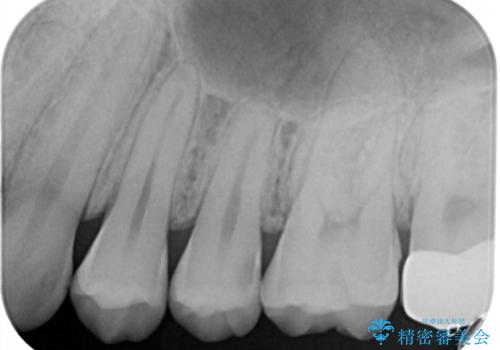

- 左上5番の虫歯治療を主訴に来院された患者様です。

セラミックでの治療を希望されたので形態・切削量を考慮しセラミックインレーでの治療を選択しました。

隣り合っている面(隣接面)は清掃がしづらく虫歯になりやすい場所です。

また、形態の再現が難しいのでインレーなどの補綴物での治療が第一選択となることが多いです。